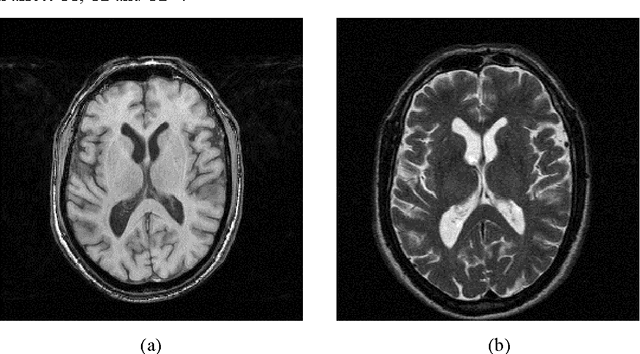

Abstract:Accumulating evidence has shown that iron is involved in the mechanism underlying many neurodegenerative diseases, such as Alzheimer's disease, Parkinson's disease and Huntington's disease. Abnormal (higher) iron accumulation has been detected in the brains of most neurodegenerative patients, especially in the basal ganglia region. Presence of iron leads to changes in MR signal in both magnitude and phase. Accordingly, tissues with high iron concentration appear hypo-intense (darker than usual) in MR contrasts. In this report, we proposed an improved binary hypointensity description and a novel nonbinary hypointensity description based on principle components analysis. Moreover, Kendall's rank correlation coefficient was used to compare the complementary and redundant information provided by the two methods in order to better understand the individual descriptions of iron accumulation in the brain.